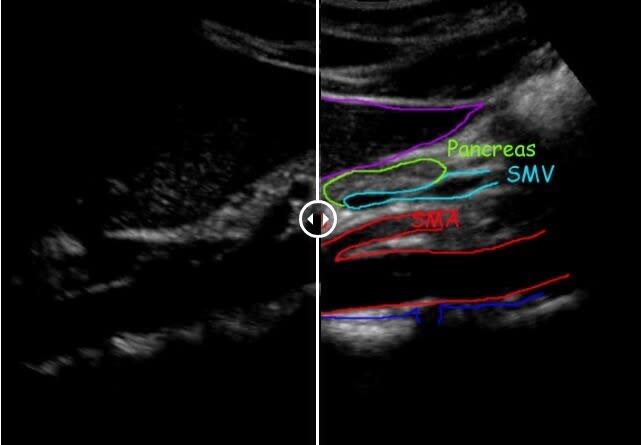

This ultrasound scan is used to detect abdominal aortic aneurysms (AAA's) and also for the monitoring and follow-up assessment of an aortic dilation.